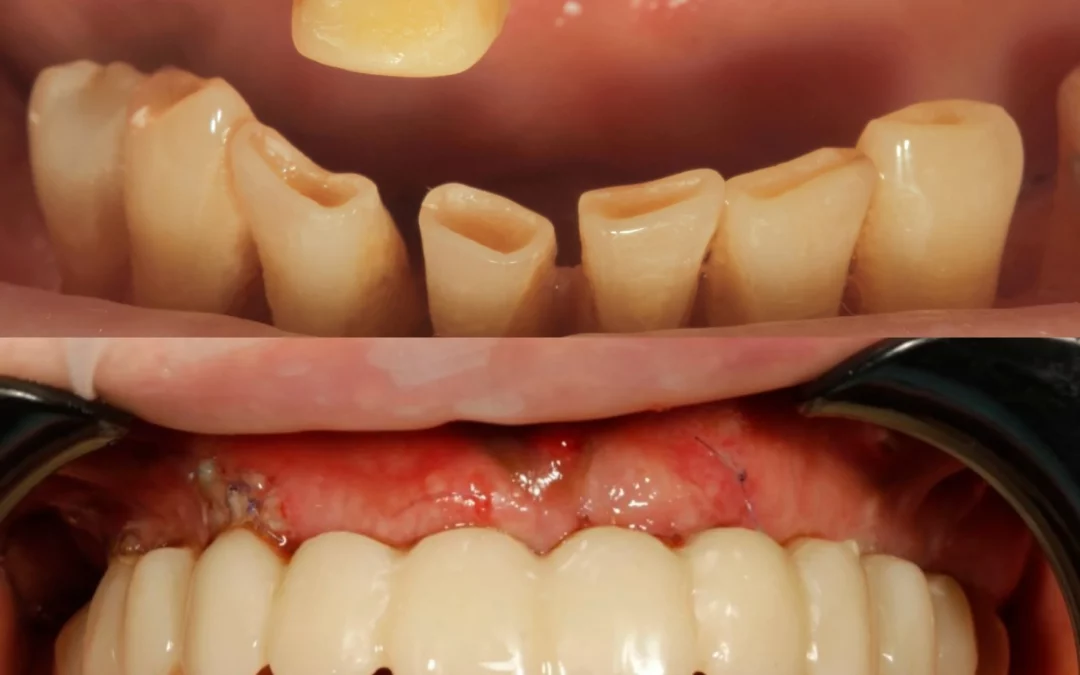

Промежуточный этап тотальной реабилитации. Сделано: 1. Снятие несостоятельных реставраций на н/ч 2. MockUp на нижние передние зубы, новые временные протезы на имплантаты, установленные 7 лет назад, на новой...